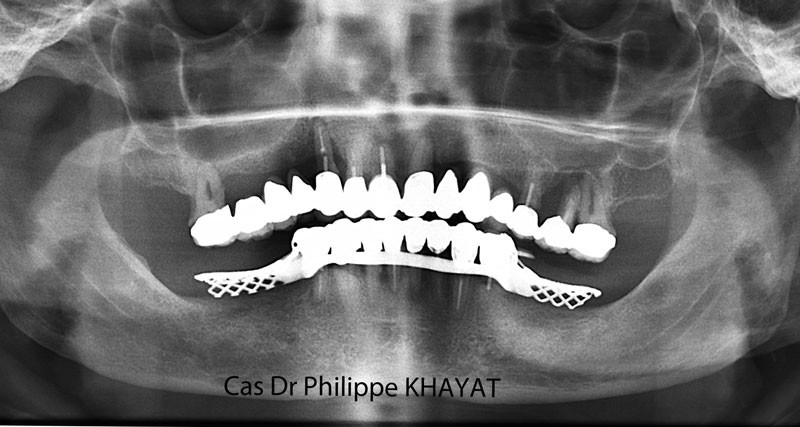

Philippe Khayat parlera de la « Mise en charge immédiate de l’arcade complète maxillaire » et il mettra l’accent sur les techniques qu’il a sélectionnées au terme de quatorze années d’expérience (fig. 1 à 4).